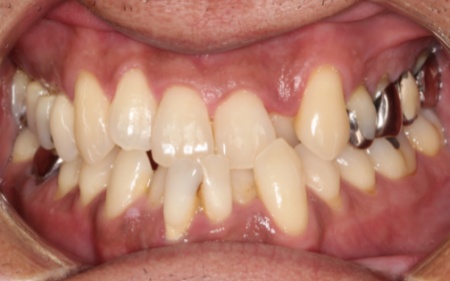

治療前

拝見すると、上の前歯3本(左右の中切歯/1番、右の側切歯/2番)が、他の歯より前に飛び出ている「上顎前突(じょうがくぜんとつ)」、いわゆる出っ歯で、真ん中は2本分が連結している保険範囲内の古い被せ物が入っていました。

出っ歯だと物が噛みにくいため、唇も閉じにくい様子でした。

また、左の前歯(側切歯)は通常より小さいため隣の歯(中切歯)とのサイズ差が大きく、見た目のバランスが合っていませんでした。